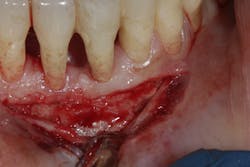

- Proper surgical technique including incision, flap design, and complete detoxification of bony defect and root apices (figures 3 and 3a)